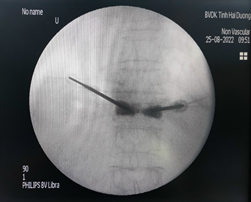

Bước 1: Xác định điểm vào thân đốt sống tổn thương thông qua cuống trên C-arm

Bước 5: Đây là bước quan trọng nhất khi thực hiện kỹ thuật, xi măng sinh học sẽ được bơm qua kim định vị rỗng rỗng vào thân đốt sống bị xẹp. Tốc độ bơm phải chậm và được theo dõi chặt chẽ của bác sĩ thông qua C-arm và những biểu hiện lâm sàng của bệnh nhân như tình trạng đau hay cử động hai chân.

Bước 6: Để chắc chắn xi măng sinh học chỉ khu trú trong thân đốt sống, bác sĩ sẽ kiểm tra bằng C-arm hai bình diện thêm một lần nữa.